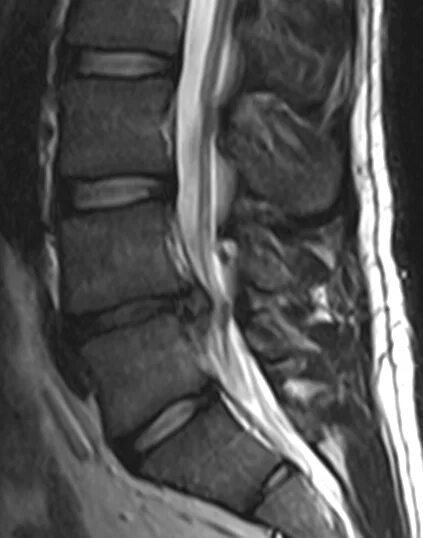

Грыжа диска мрт